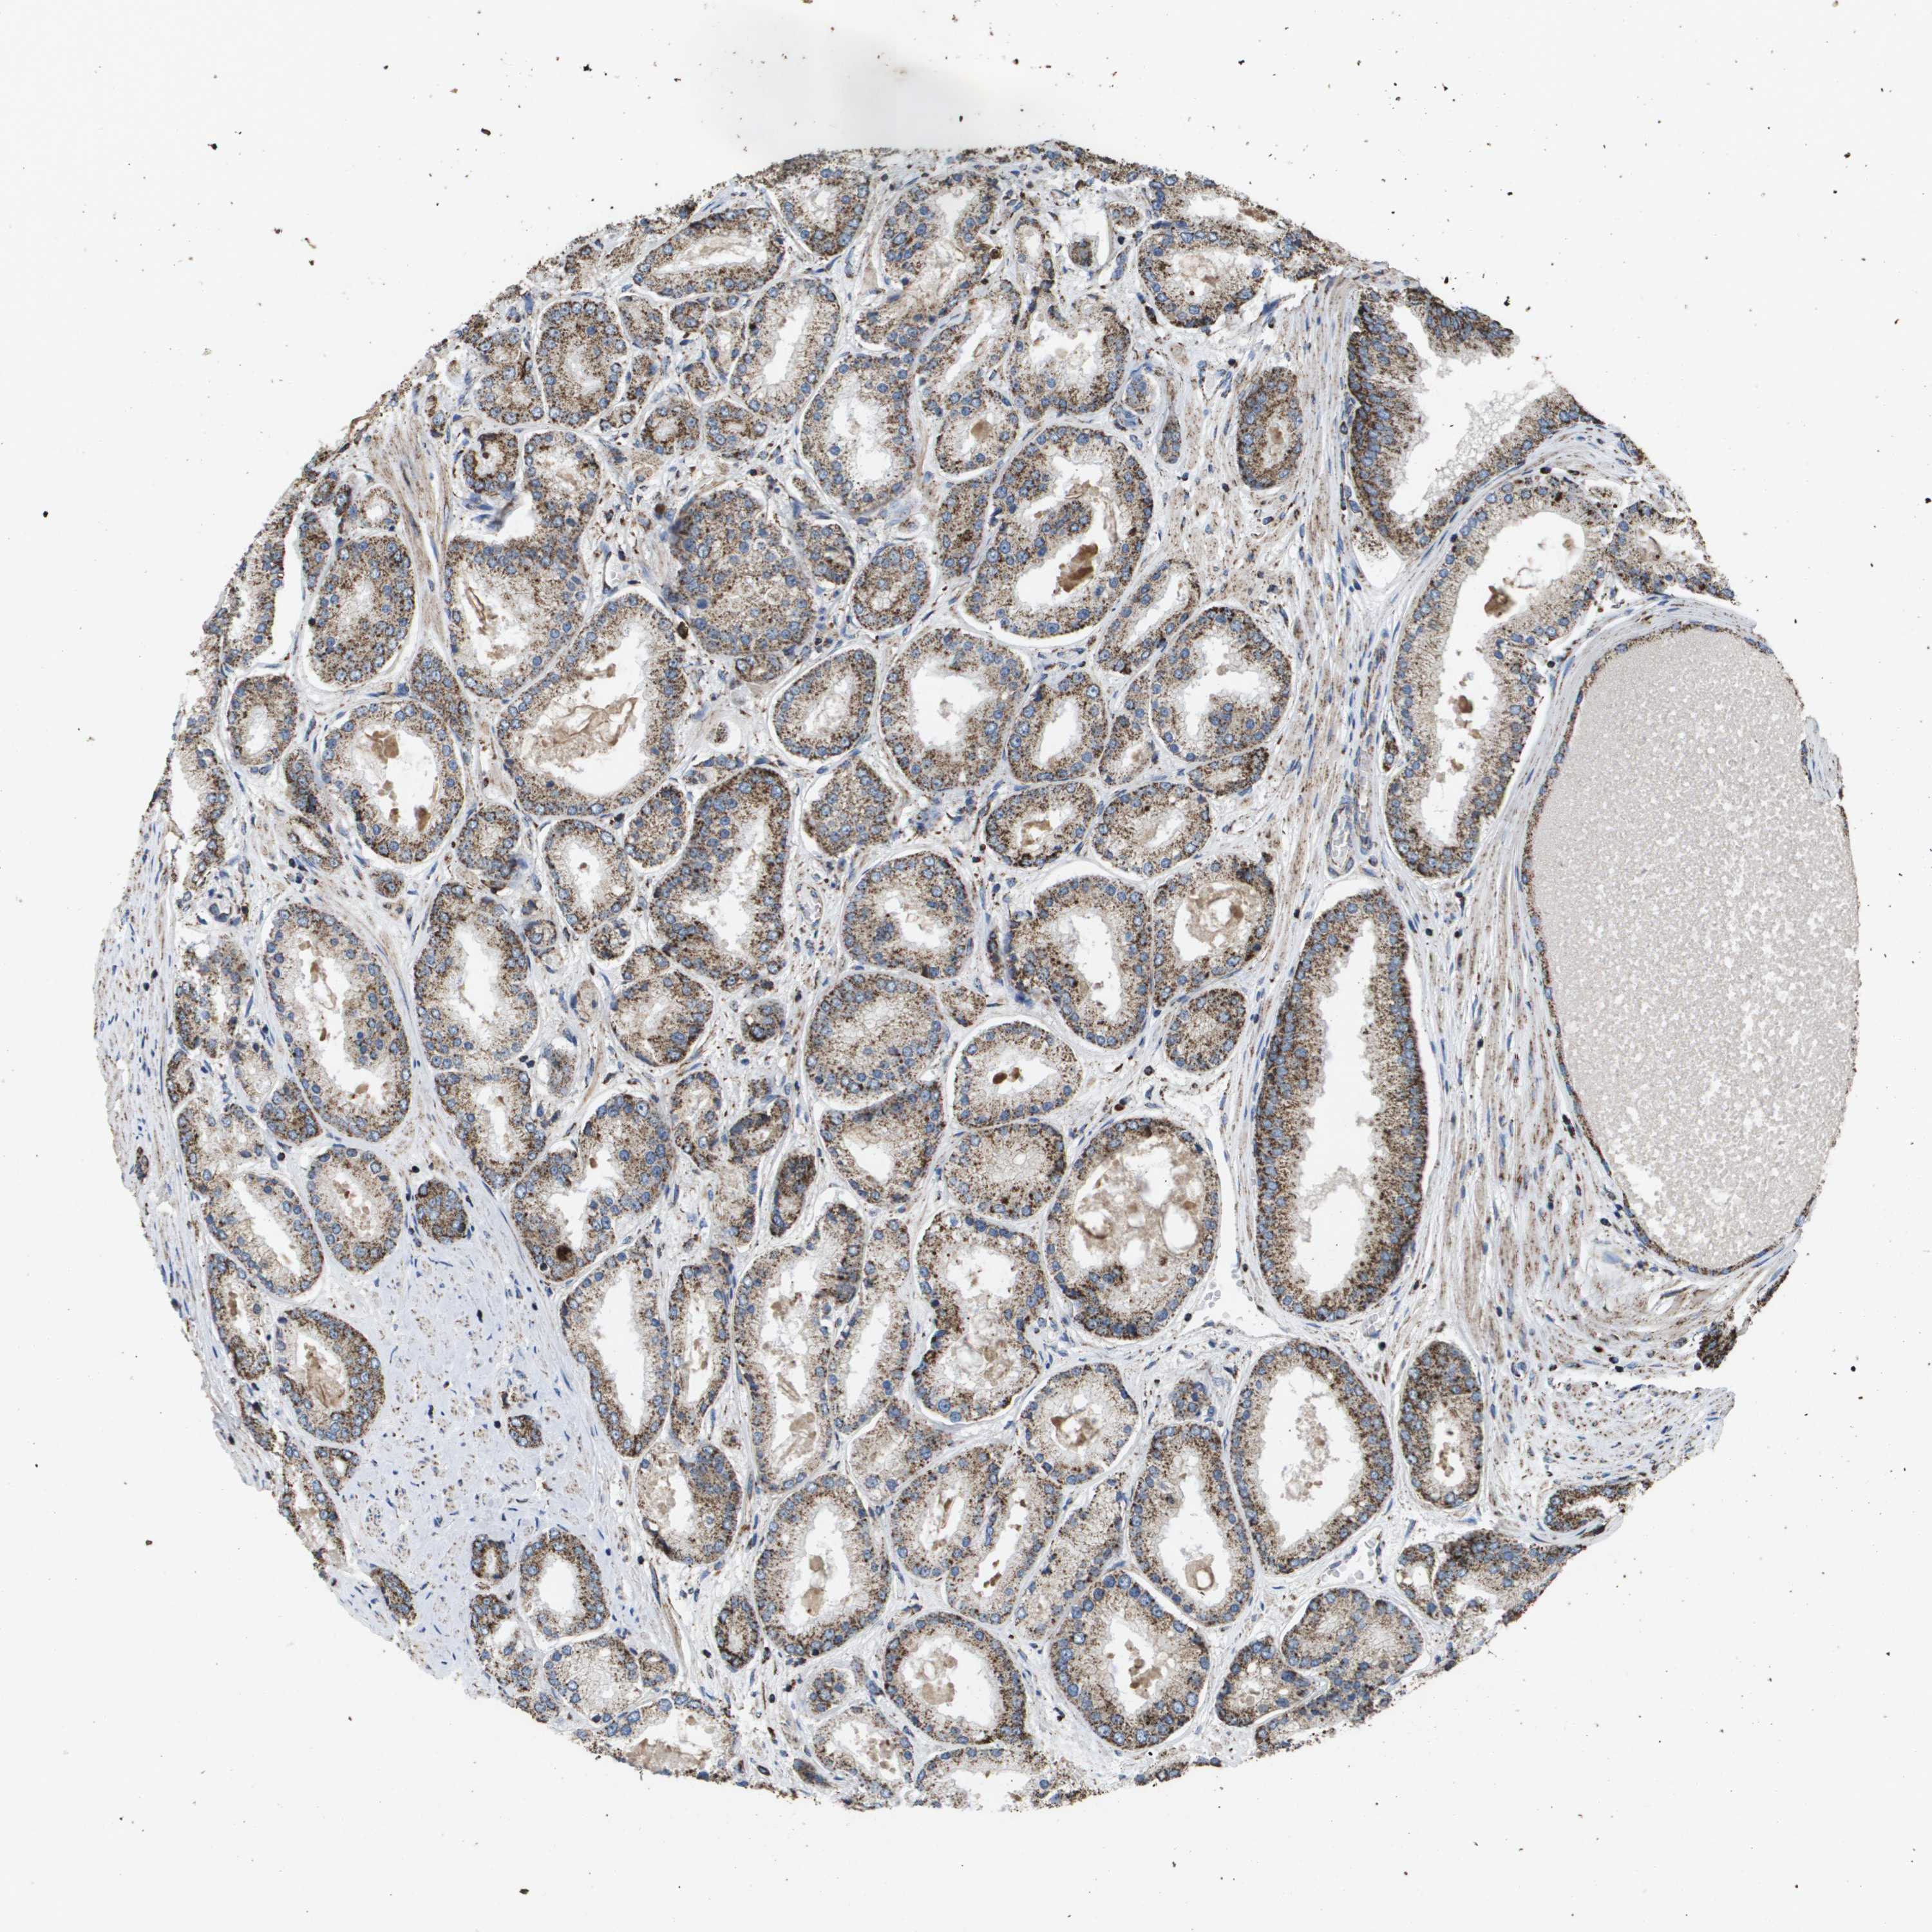

PROSTATE CANCER - Protein expressioni

A mouse-over function shows sample information and annotation data. Click on an image to view it in a full screen mode. Samples can be filtered based on level of antibody staining by selecting one or several of the following categories: high, medium, low and not detected. The assay and annotation is described here.

Note that samples used for immunohistochemistry by the Human Protein Atlas do not correspond to samples in the TCGA dataset.

Antibody stainingi

Antibody staining in the annotated cell types in the current human tissue is reported as not detected, low, medium, or high, based on conventional immunohistochemistry profiling in selected tissues. This score is based on the combination of the staining intensity and fraction of stained cells.

Each image is clickable and will lead to virtual microscopy that enables deeper exploration of all samples and also displays staining intensity scores, fraction scores and subcellular localization as well as patient and tissue information for each sample.

Antibody HPA038755

Antibody HPA048272

Antibody CAB017366

Staining

High

Medium

Low

Not detected

Intensity

Strong

Moderate

Weak

Negative

Quantity

>75%

75%-25%

<25%

None

Location

Nuclear

Cytoplasmic/membranous

Cytoplasmic/membranous,nuclear

Adenocarcinoma, NOS

Adenocarcinoma, High grade

Adenocarcinoma, Low grade